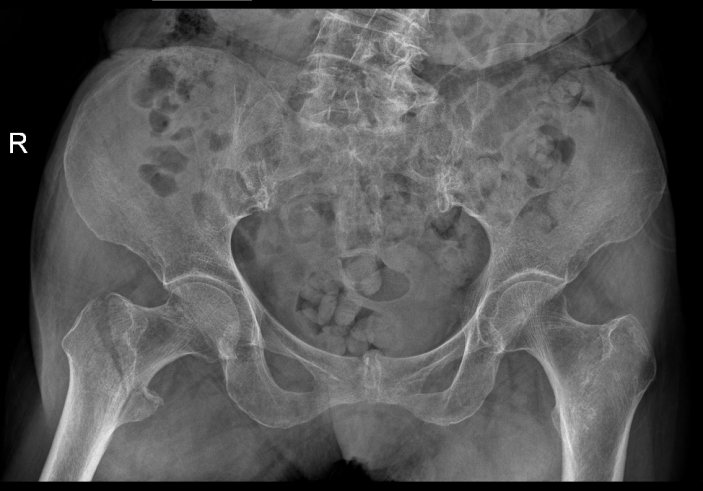

經過CT檢查發現老人家的左股骨頸骨折。此外還伴有老年性骨質疏松、高血壓病、低鈉低鉀血症等疾病。骨科吳志斌主任随即請内科、麻醉科專家會診。予監控血壓、血糖,抗骨質疏松、營養心肌等對症治療。待患者病情穩定、可耐受手術後進行手術治療。

吳志斌主任通過CT+三維重建先行拟定詳細手術方案,提前做了精心準備。根據患者的年齡特征,爲其選擇最佳的半髋置換方案,并采用雙動人工股骨頭,提高活動範圍,減少髋臼磨損。

△術前